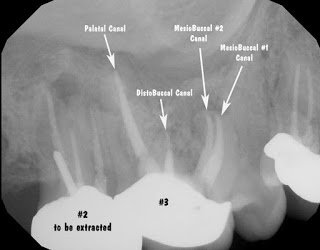

Endodontic diagnosis, including CBCT, determines that tooth #2 has a prior root canal with a root fracture and extraction is recommended. Tooth #3 has a prior RCT with apical abscess – caused by a missed MB#2 canal during the initial root canal treatment. Retreatment of the root canal #3 is recommended.

The endodontists at Superstition Springs Endodontics are experts in endodontic diagnosis and have extensive experience with CBCT. In addition, endodontists are specially trained to perform the most difficult endodontic cases. Maxillary molars, most closely associated with the maxillary sinus, almost always have 4 canals.

A common reason for root canal failure on Mx molars is inadequte cleaning, and often completely missing the MB#2 canal. Endodontists using an operating microscope are able to find and treat the MB#2 (4th canal) more effectively and efficiently. Endodontist are also trained to perform endodontic microsurgery when traditional endodontic therapy is unsuccessful.